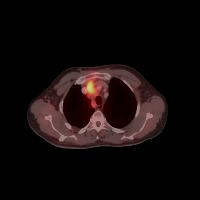

Diagnostic Aid in Medical Imaging: Radiologists could use this model to identify and characterize lymph node tumors in CT scans, assisting in early detection and diagnosis of potential cancerous growths.

Medical Research: Researchers might employ the model to study the characteristics and progressions of various types of lymph node tumors, towards producing more effective treatments and prevention strategies.

Training Medical Students: This model could serve as an invaluable tool for training medical students or residents in radiology, allowing them to familiarize themselves with the appearance and location of different lymph nodes, as well as to recognize varied tumor classifications.

Telemedicine: In remote or rural areas lacking immediate access to expert radiologists, this model can come handy as it assists primary care providers or mid-level practitioners in identifying lymph node tumors and making more effective referrals.

Second Opinion: Patients with possible lymph node tumors might use the model as a 'second opinion' to verify diagnoses, ensuring there are no oversights in their scans.